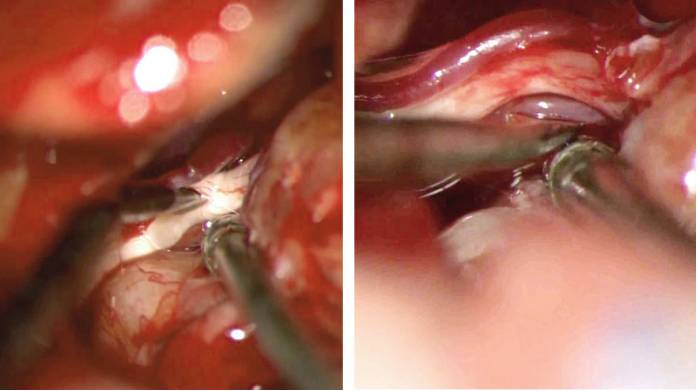

图9. 上两图为展示轮廓化IAC的术中照,下图为展示沿IAC中部切开硬膜并往内耳门上下两端延伸的手绘图。操作过程中切勿损伤面神经和岩静脉。切开的硬膜瓣分别往上和往下牵开,然后在肿瘤与小脑之间垫入棉片。